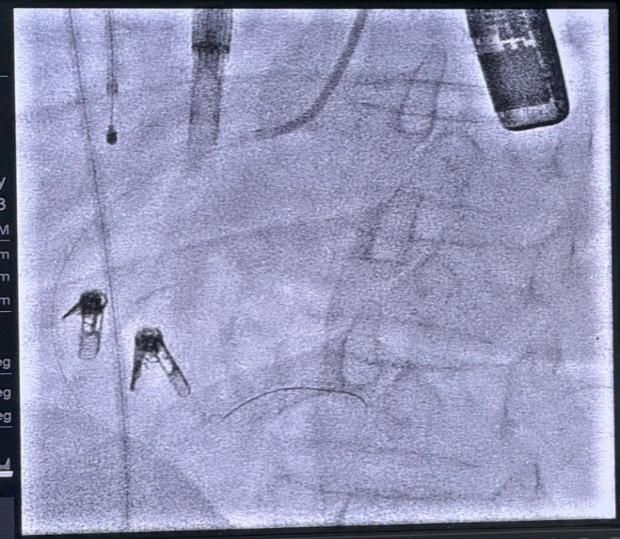

DSA下夹合器形态

结合术前CT与TEE综合评估,本例患者三尖瓣环严重扩张,反流位置主要集中在前隔瓣叶对合处以及中央处,手术操作难度较高,拟采用两个夹子来缩小瓣环尺寸以改善瓣叶对合,从而降低三尖瓣反流。手术当日,在韩东刚教授精湛的超声技术引导和麻醉团队的密切配合下,邓捷主任、王新宏教授的心脏瓣膜团队术中精准释放两枚K-Clip夹子后,患者三尖瓣瓣环面积明显缩小,瓣叶对合情况显著改善,反流程度由5+降低至2+,成功对严重扩张的三尖瓣瓣环进行了修复和成形。整个手术过程顺利,患者生命体征平稳。